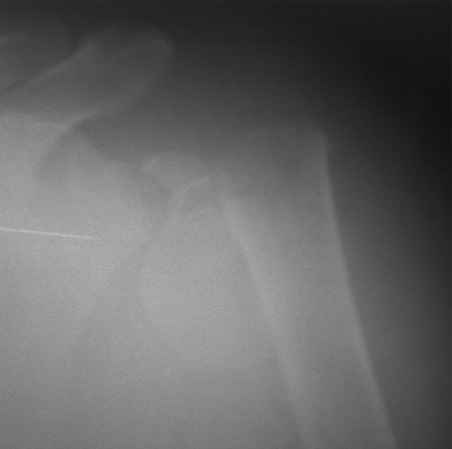

Пациентка 51 год. Вторые сутки после травмы. Поступила в травматологическое отделение с диагнозом переломовывих шейки плеча.

Местно индуративный отёк, гематома. Выскажите, пожалуйста, ваше мнение относительно тактики лечения

Судя по X-Ray у больной имеется оскольчатый перелом анатомической шейки плечевой кости с вывихом головки.... в данной ситуации предпочтительнее как мне кажеться будет не синтез, а первичное протезирование плечевого сустава.

Конечно с остеосинтезом лучше не тянуть, но с учетом выраженного отека и, соответственно страдания мягких тканей, 10-12 дней в запасе есть. За это время спокойно можно подготовить фиксатор. Я бы остановился на пластине. Если есть возможность - для планирования операции очень поможет рентгеновская КТ с 3D реконструкцией. Мы подобные переломо-вывихи синтезируем из чрездельтовидного доступа, который можно расширить в сторону клювовидного отростка. Будет однозначно меньше кровопотеря, легче выполнить ревизию суставной поверхности лопатки. По ходу вмешательства желателен ЭОП-контроль. Обязательно подшейте к пластине(с натяжением) мелкие фрагменты большого бугорка, которые видны на представленной Rg. От этой мелочи зависит дальнейшая функция. Не стесняйтесь в случае сомнения применить отводящую шину.